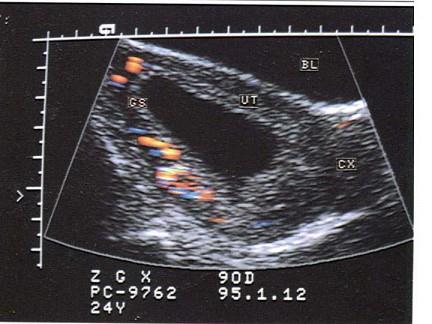

问题 女性,25岁,停经55天,腹痛、阴道出血1周。尿妊娠试验阴性。结合超声图像,最可能的诊断为?(?)

选项 A.正常早孕 B.完全流产 C.先兆流产 D.难免流产 E.宫腔积液

答案 D